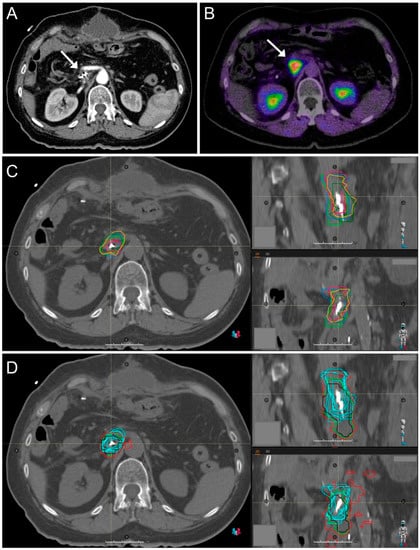

2.1. CT Imaging and Target Volume Definition by Radiation Oncologists

2.2. FAPI-PET/CT Imaging

2.3. Automated Target Volume Definition in FAPI-PET/CT-Scans

2.4. Image Registration

3.2. Target Volume Definition by Radiation Oncologists

3.3. Interobserver Variability